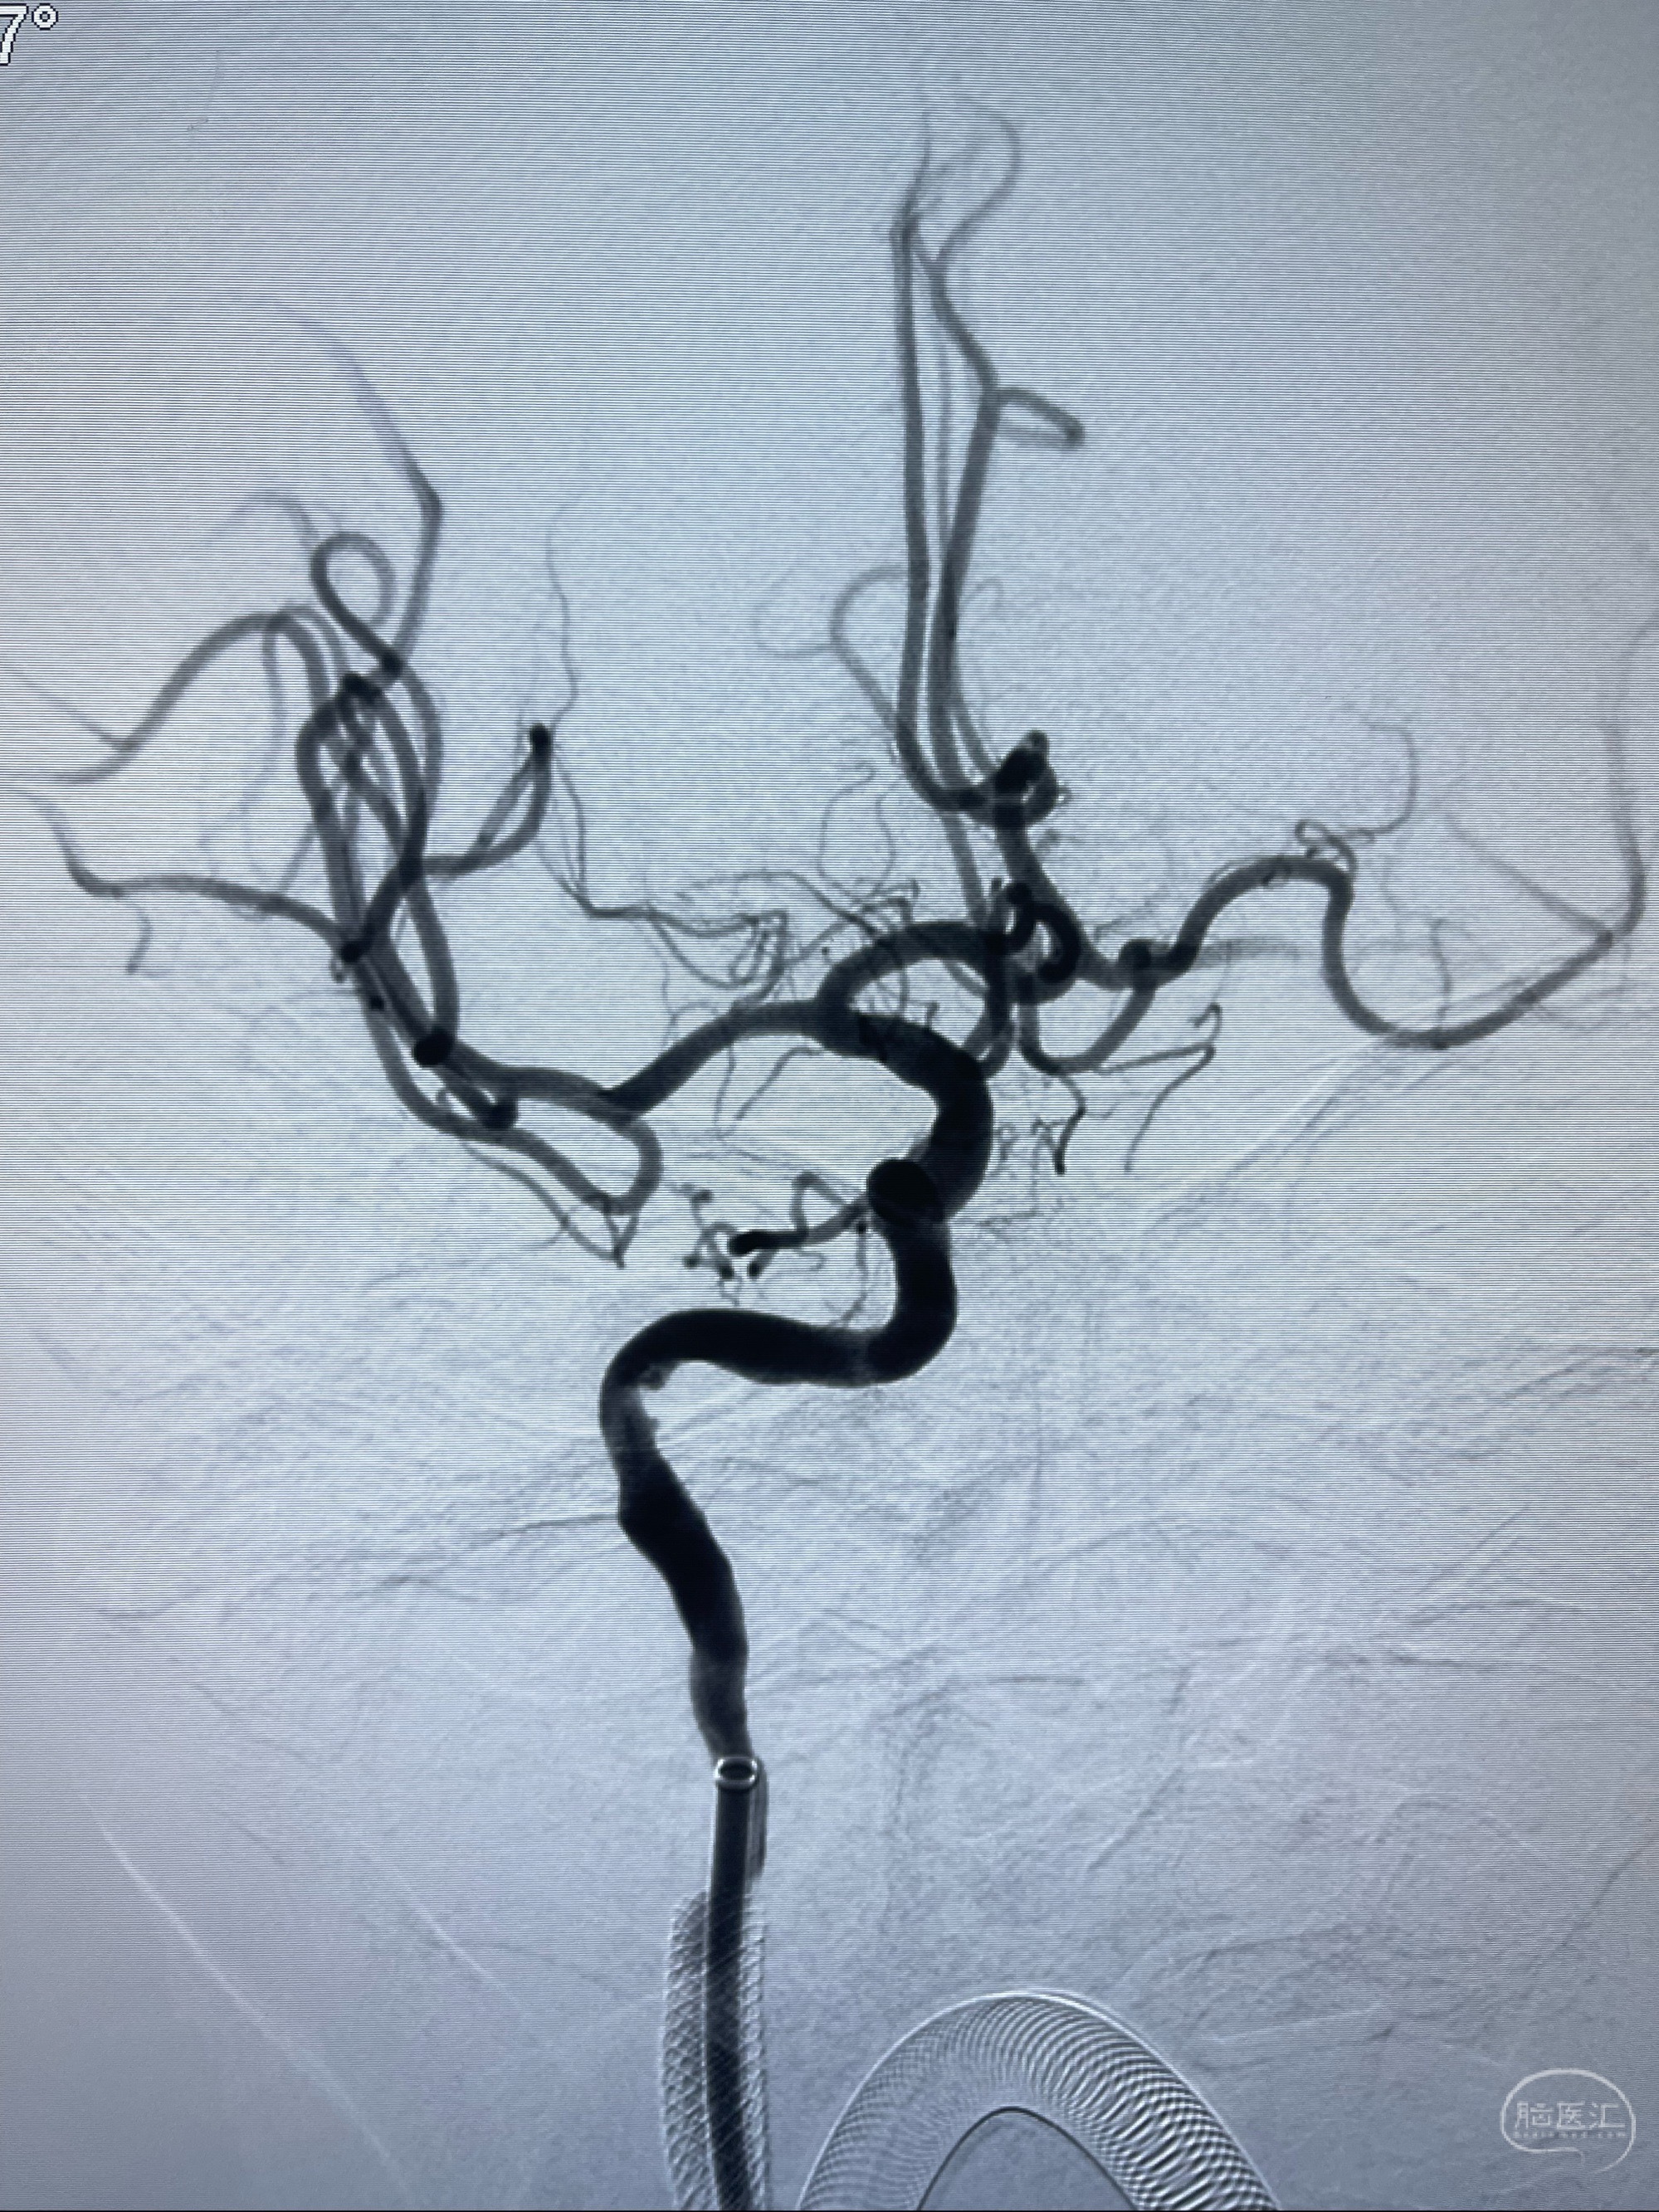

2023-07-10DSA:右侧颈内动脉岩骨段夹层伴中偏重度狭窄改变,左侧颈总动脉闭塞、右侧颈外动脉由右侧肋颈干甲颈干吻合代偿

箭头所示为颈内动脉岩骨段重度狭窄,结合MRI,考虑为肿瘤侵犯右侧颈内动脉

箭头以近至支架段管腔不规则狭窄

经导引导管造影显示支架远端颈内动脉不规则狭窄伴局部充盈缺损,同时行全身肝素化5ml